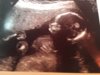

OUL i dag! perfekt liten frøken som ville posere pent!